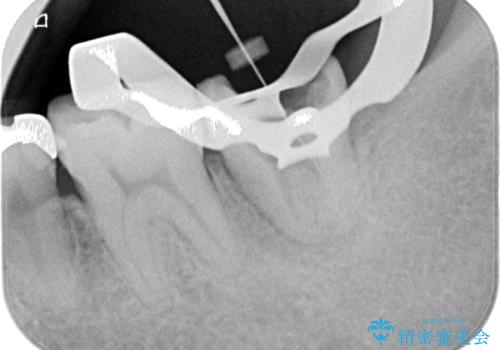

上顎の歯をアンカースクリューを用いた部分矯正により位置を修正し、根管治療後にPGAクラウンにて補綴治療を行うこととしました。